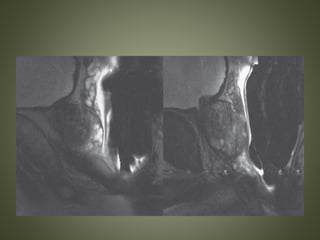

DYNAMIC CONTRAST ENHANCED MRI

• Early arterial enhancement and washout on

DCE images.

• Raw data from these dynamic sequences is

used to generate perfusion maps in which the

prostate can be evaluated for focal areas of

altered wash-in/washout kinetics and capillary

permeability

• average enhancement and

washout throughout the

gland, typical of normal

prostate tissue

type 1

curve

• early and intense enhancement

followed by slow washout, a

pattern that can be seen in BPH,

prostatitis, and multifocal low-

grade tumor

type 2

• is characterized by early and

intense contrast enhancement

followed by rapid washout, a

feature of high-grade tumors

type 3

SEMINAL VESICLE INVASION

• Loss or disruption of the normal seminal vesicle

architecture

• Replacement of the T2-hyperintense seminal vesicle

with hypointense tumor

• Obliteration of the normal prostate–seminal vesicle

angle